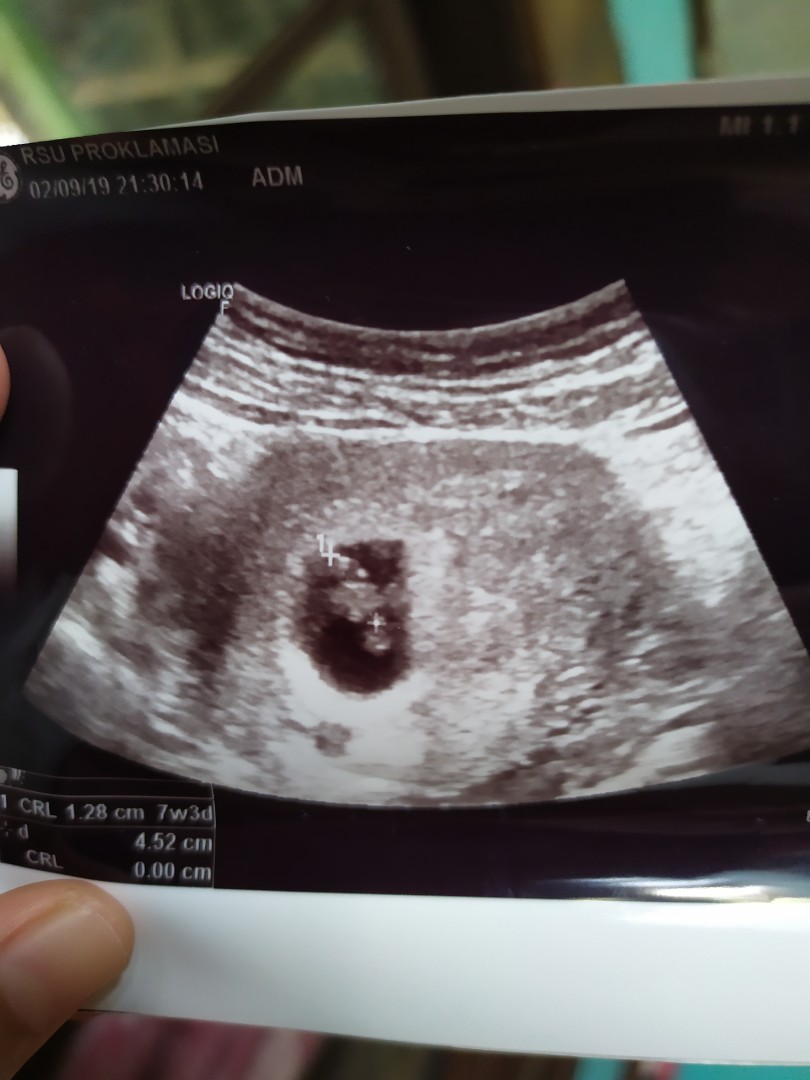

Hamil 7w 5d

Sedih yah bun...hamil 7w 5d pas usg blm ada bayinya. katong gede tp kosong. disuruh balik 2 minggu lg. kalo ga ada isi nya juga kemungkinan bs dikuret. udh di kasih vitamin n penguat kandungan sm dokter krna ada ngeflek tp dikit banget hanya nempel di tisu pas lap itu pun dikit sekali ga smpi setetes. apakah bunda pernah mengalami hal yg sama, dan gimana hasil nya? rasanya 2 minggu lagi ak ga berani balik ke dokter karna takut. hiks... saya udh konsul sm 4 dr.spog dsn hasil nya sama disuruh balik lg 2 minggu.